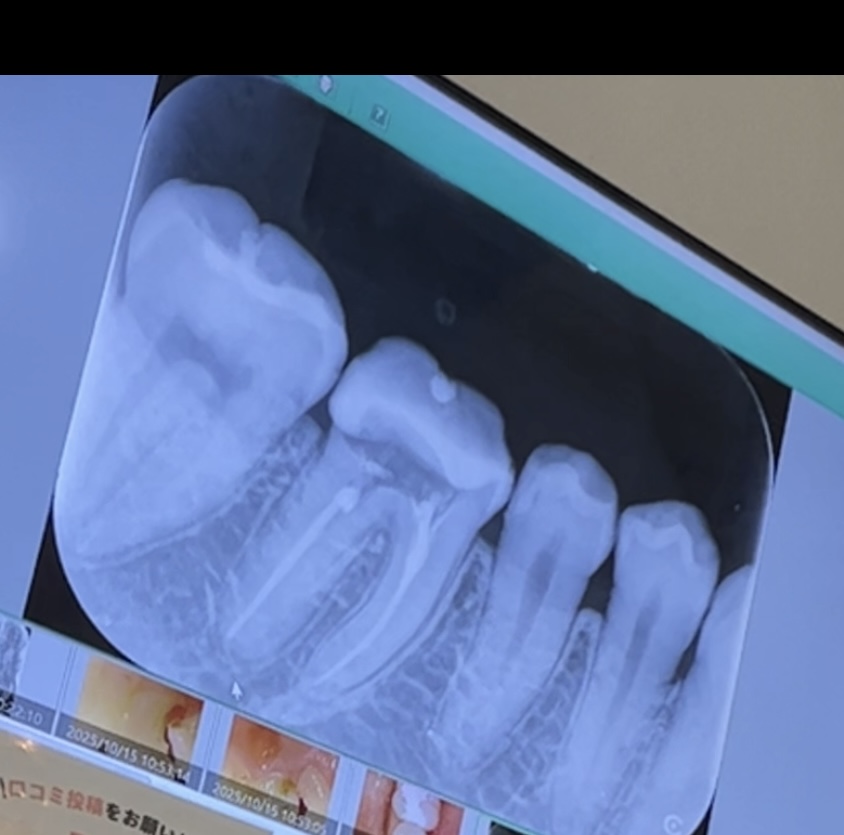

根(神経)の治療に関するお悩み相談